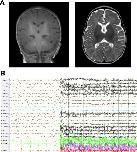

FIGURE 1

Brain MRI and EEG features of the patient with the M641I variant. (A) MRI of the brain at 3âmonths of age was normal. (B) Ictal EEG at 9âmonths of age showed electro decrement superimposed with fast activity and myogenic artifacts in a patient with typical epileptic spasms.